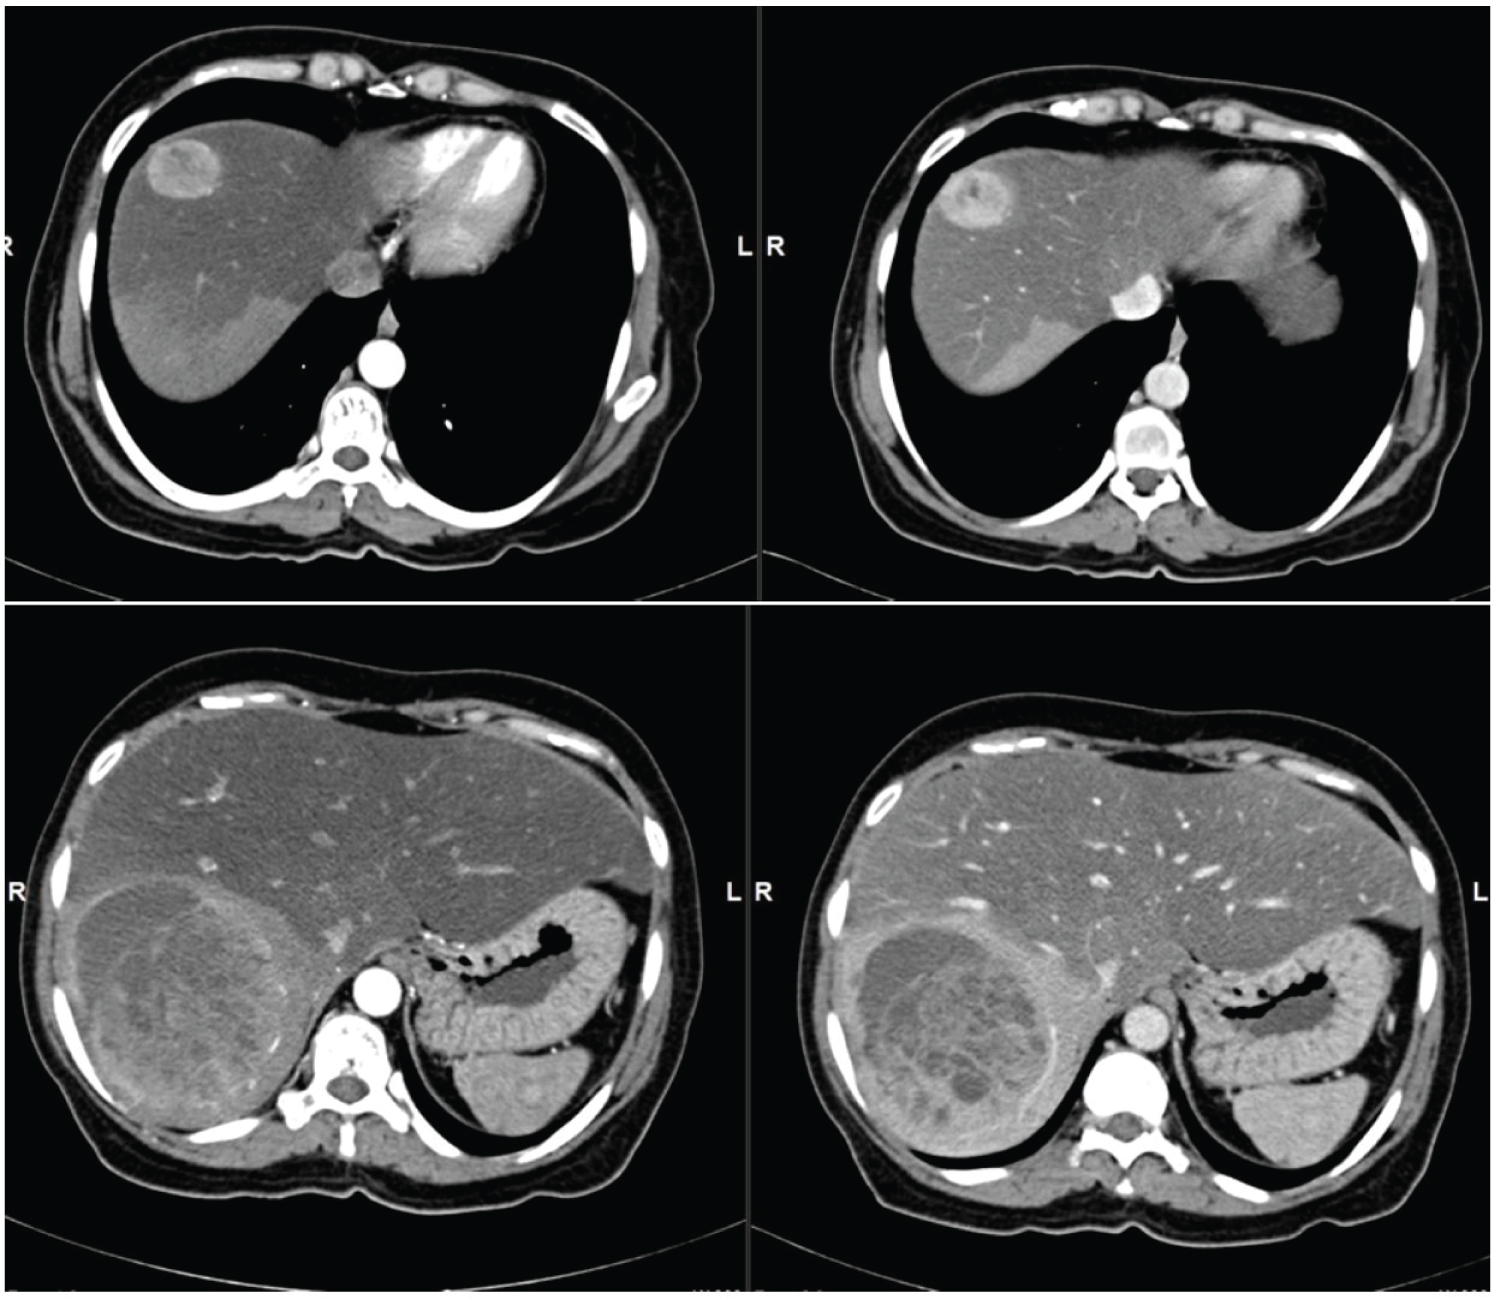

Our patient is a middle aged female who presented with vague abdominal pain and chronic diarrhoea. CECT shows two well defined lesions in segment VII/VIII and VI with intense marginal nodular enhancement in arterial phase and no washout in portal phase (Figure 2).

Figure 2: Primary NET. (a,b) Contrast enhanced CT axial sections shows a well-defined small round lesion in segment VII/VIII with intense marginal nodular enhancement in arterial phase (a) and no washout in portal phase (b) in the background of fatty liver and areas of fat sparing; (c,d) Contrast enhanced CT axial sections shows a well defined large lesion in segment VI with intense marginal nodular enhancement in arterial phase (a) and no washout in portal phase (b) in the background of fatty liver and areas of fat sparing. View Figure 2

No evidence of any focal lesion in the entire gastrointestinal tract and tracheobronchial tree.